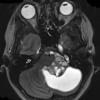

NEOPLASMS (GLIAL)

Astrocytoma, pilocytic - Microscopic (12)